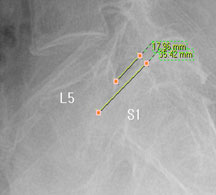

모커리한방병원 위 뼈가 50%정도 밀려나간 모습 이미지

척추전방전위증은 척추 주변, 특히 척추 후방에 있는 후관절 주변의 근육과 인대 그리고 후관절 자체가 퇴행되어 척추 뼈를 제대로 붙잡아 주지 못해 위아래 척추 뼈가 앞뒤로 밀려 나가면서 발생하는 척추질환을 말합니다.